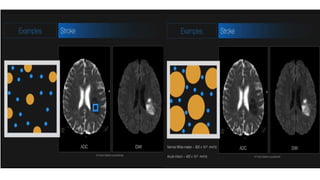

NEUROIMAGING applications :

1. Stroke

MR PERFUSION in STROKE

• DWI & PWI together are very

effective in detection of early

ischemia.

• The mismatch between PW &

DW represents potentially

salvageable tissue(PENUMBRA).